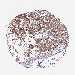

CANCER BREAST CANCER Show tissue menu

BRCA TCGA BRCA VALIDATION PROTEIN EXPRESSION